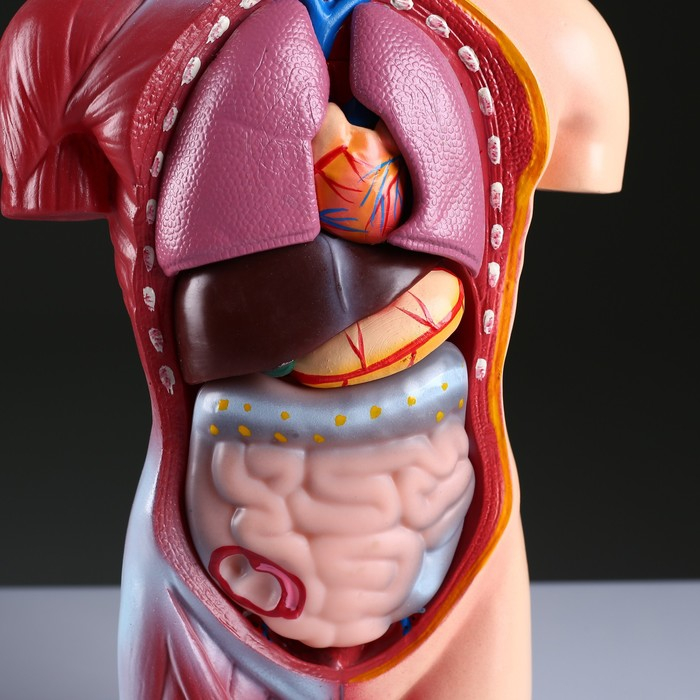

Анатомические модели